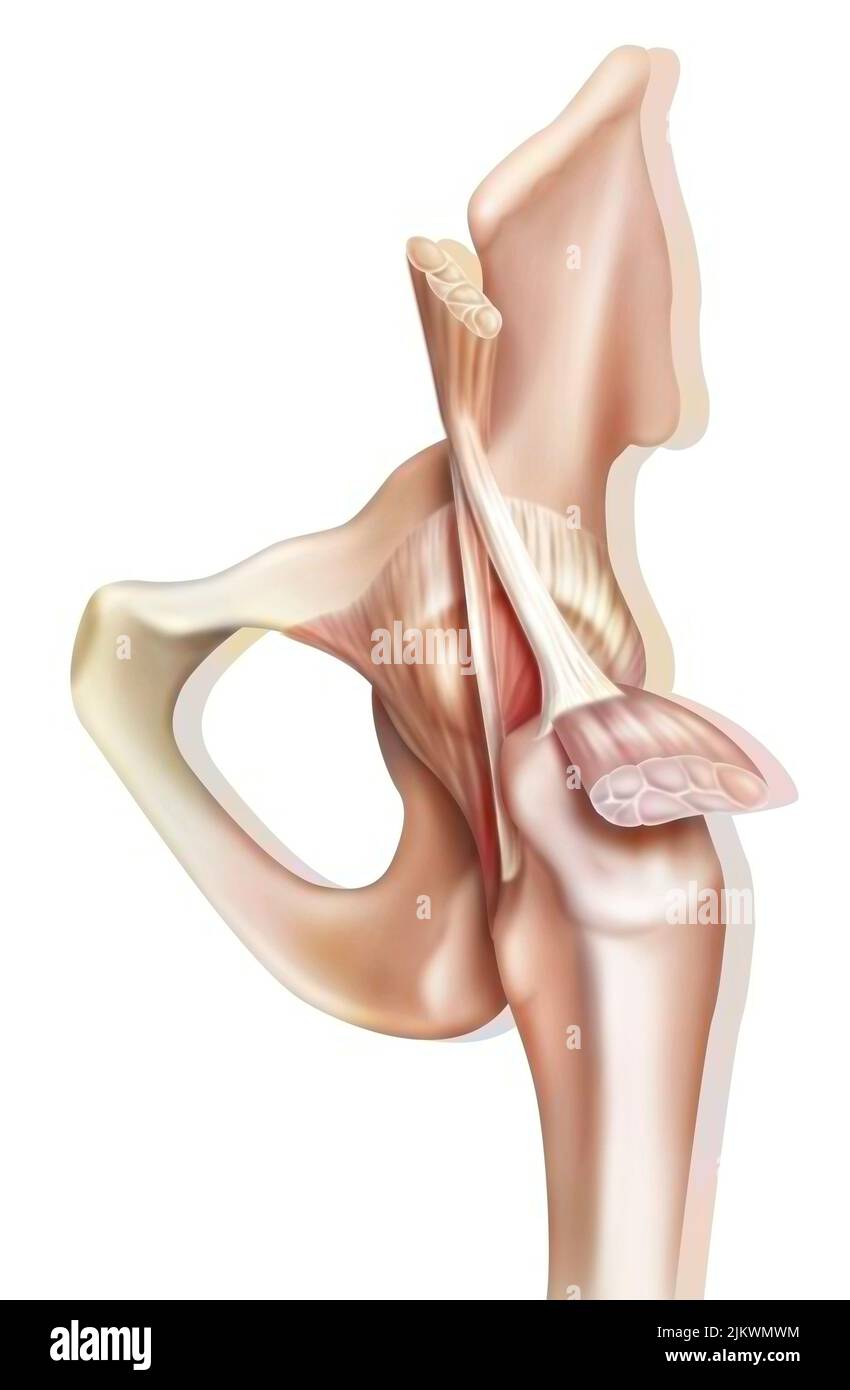

Articulation osseuse de la hanche sans et avec la capsule de l'articulation coxofémorale. Banque D'Imageshttps://www.alamyimages.fr/image-license-details/?v=1https://www.alamyimages.fr/articulation-osseuse-de-la-hanche-sans-et-avec-la-capsule-de-l-articulation-coxofemorale-image476923594.html

Articulation osseuse de la hanche sans et avec la capsule de l'articulation coxofémorale. Banque D'Imageshttps://www.alamyimages.fr/image-license-details/?v=1https://www.alamyimages.fr/articulation-osseuse-de-la-hanche-sans-et-avec-la-capsule-de-l-articulation-coxofemorale-image476923594.htmlRF2JKWMWE–Articulation osseuse de la hanche sans et avec la capsule de l'articulation coxofémorale.

Anatomie de l'articulation coxofémorale (hanche) avec les muscles, les tendons. Banque D'Imageshttps://www.alamyimages.fr/image-license-details/?v=1https://www.alamyimages.fr/anatomie-de-l-articulation-coxofemorale-hanche-avec-les-muscles-les-tendons-image476923600.html

Anatomie de l'articulation coxofémorale (hanche) avec les muscles, les tendons. Banque D'Imageshttps://www.alamyimages.fr/image-license-details/?v=1https://www.alamyimages.fr/anatomie-de-l-articulation-coxofemorale-hanche-avec-les-muscles-les-tendons-image476923600.htmlRF2JKWMWM–Anatomie de l'articulation coxofémorale (hanche) avec les muscles, les tendons.